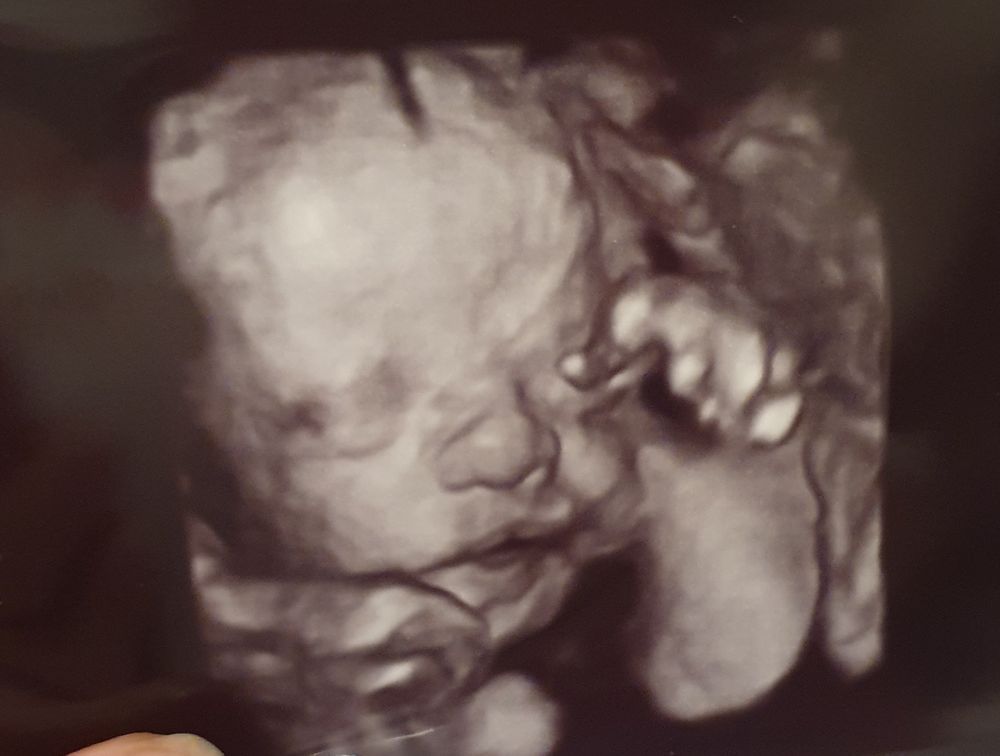

Сходила сегодня на допплерометрию, заодно сынишку показали в 3д. Уже есть щёчки, такой хорошенький! 1200 гр и 35смню ростом! Всего 8 недель и малыш будет доношен.